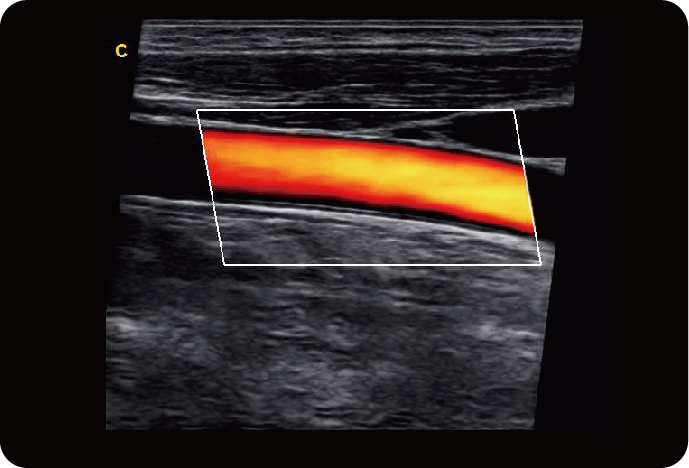

Линейный